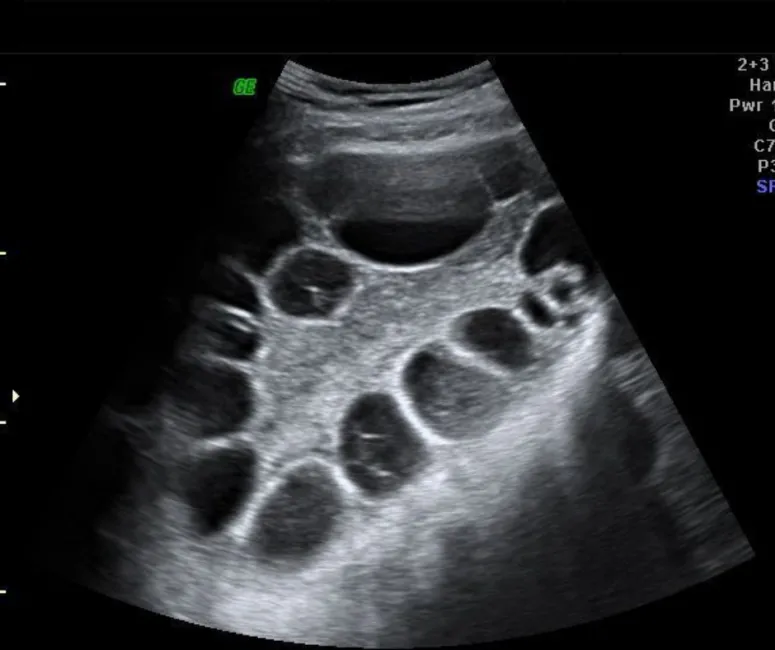

• Antral follicle count via vaginal ultrasound